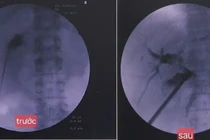

Tán sỏi túi mật xuyên gan qua da

Bệnh viện Nhân dân 115 (TP HCM) cho biết vừa thực hiện thành công ca tán sỏi túi mật xuyên gan qua da đầu tiên.

Ngày 7/8, Bệnh viện Nhân dân 115 (TP HCM) cho biết, bệnh viện đã thực hiện thành công ca tán sỏi túi mật xuyên gan qua da đầu tiên tại thành phố – một kỹ thuật hiện đại giúp điều trị sỏi mật hiệu quả mà không cần phẫu thuật cắt túi mật.

Đây là tin vui cho những người bệnh bị sỏi túi mật có nguy cơ phẫu thuật cao, nhiều bệnh nền hoặc mong muốn giữ lại túi mật vì lý do sức khỏe lâu dài.